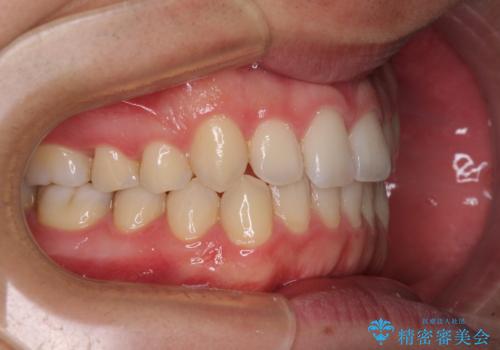

狭い歯列と前歯のデコボコ インビザラインによる矯正治療

- 上下前歯のデコボコを気にして来院された患者様です。

インビザラインによる上下歯列の拡大と、IPR(歯と歯の間を削る)にるスペースの獲得により、前歯のデコボコと狭い歯列を改善することとしました。

比較的軽度な歯列不正であったため、治療期間はそれほど長くはならないと予想されました。

しかしながら、あまりしっかりとマウスピースを装着していなかったため、思いの外期間が長引いてしまいました。

また、仕上がりの歯列にも若干の叢生が残ってしまいました。